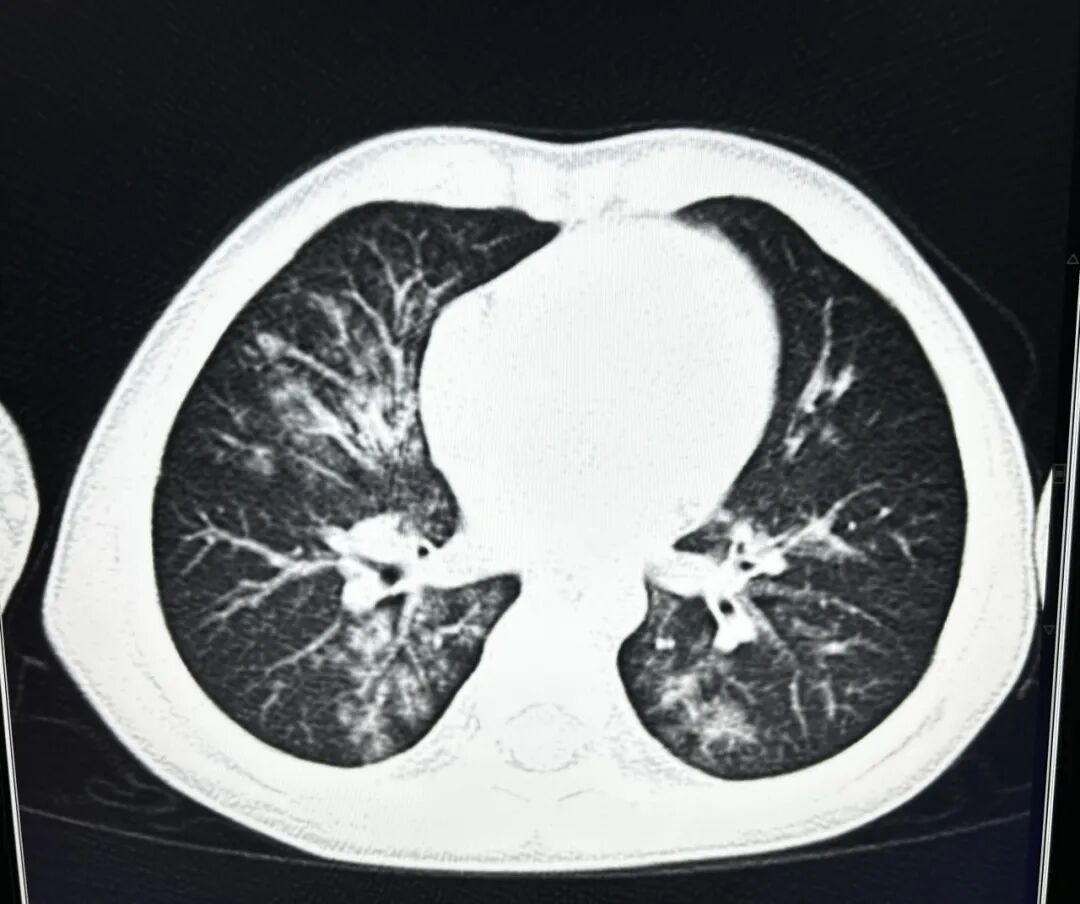

案例1、3岁的患儿平片未能明确显示肺部炎症,CT扫描显示双肺多发炎症。